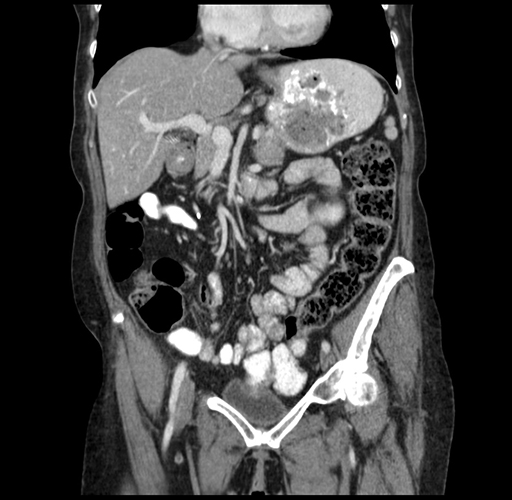

Pre-Chemo: Coronal Venous

Coronal Venous